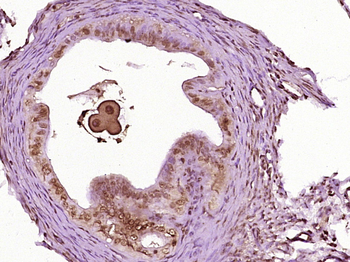

应用稀释比例:WB=1:500-2000, IHC-P=1:100-500, IHC-F=1:100-500, IF=1:100-500